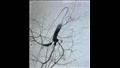

وأوضح الدكتور علاء عطية، عميد كلية الطب ورئيس مجلس إدارة المستشفيات الجامعية، أنه بعد الانتهاء من العملية تم نقل المريضة إلى العناية المركزة لمتابعة حالتها، حيث لوحظ بعد العملية لمدة 3 ساعات وجود نزيف داخلي لكون المريضة تعاني من نقص في الصفائح الدموية وعوامل التجلط، الأمر الذي استدعى تكوين فريق مشترك بين قسم أمراض النساء والتوليد وقسم الأشعة التداخلية وقسم التخدير والعناية المركزة لإجراء التدخل المناسب لإنقاذ حياة المريضة.